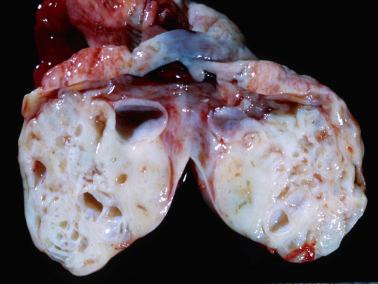

Gross features ( figs. 14.51 14.52 )

• CCCs are typically unilocular or less often multilocular cysts with polypoid intraluminal masses to nonspecific solid or solid and cystic masses. Some cysts may be grossly recognizable as endometriotic. CCCs with an adenofibromatous component may exhibit the gross features of the latter, as noted above.

Fig. 14.51, Clear cell carcinoma arising in an endometriotic cyst.